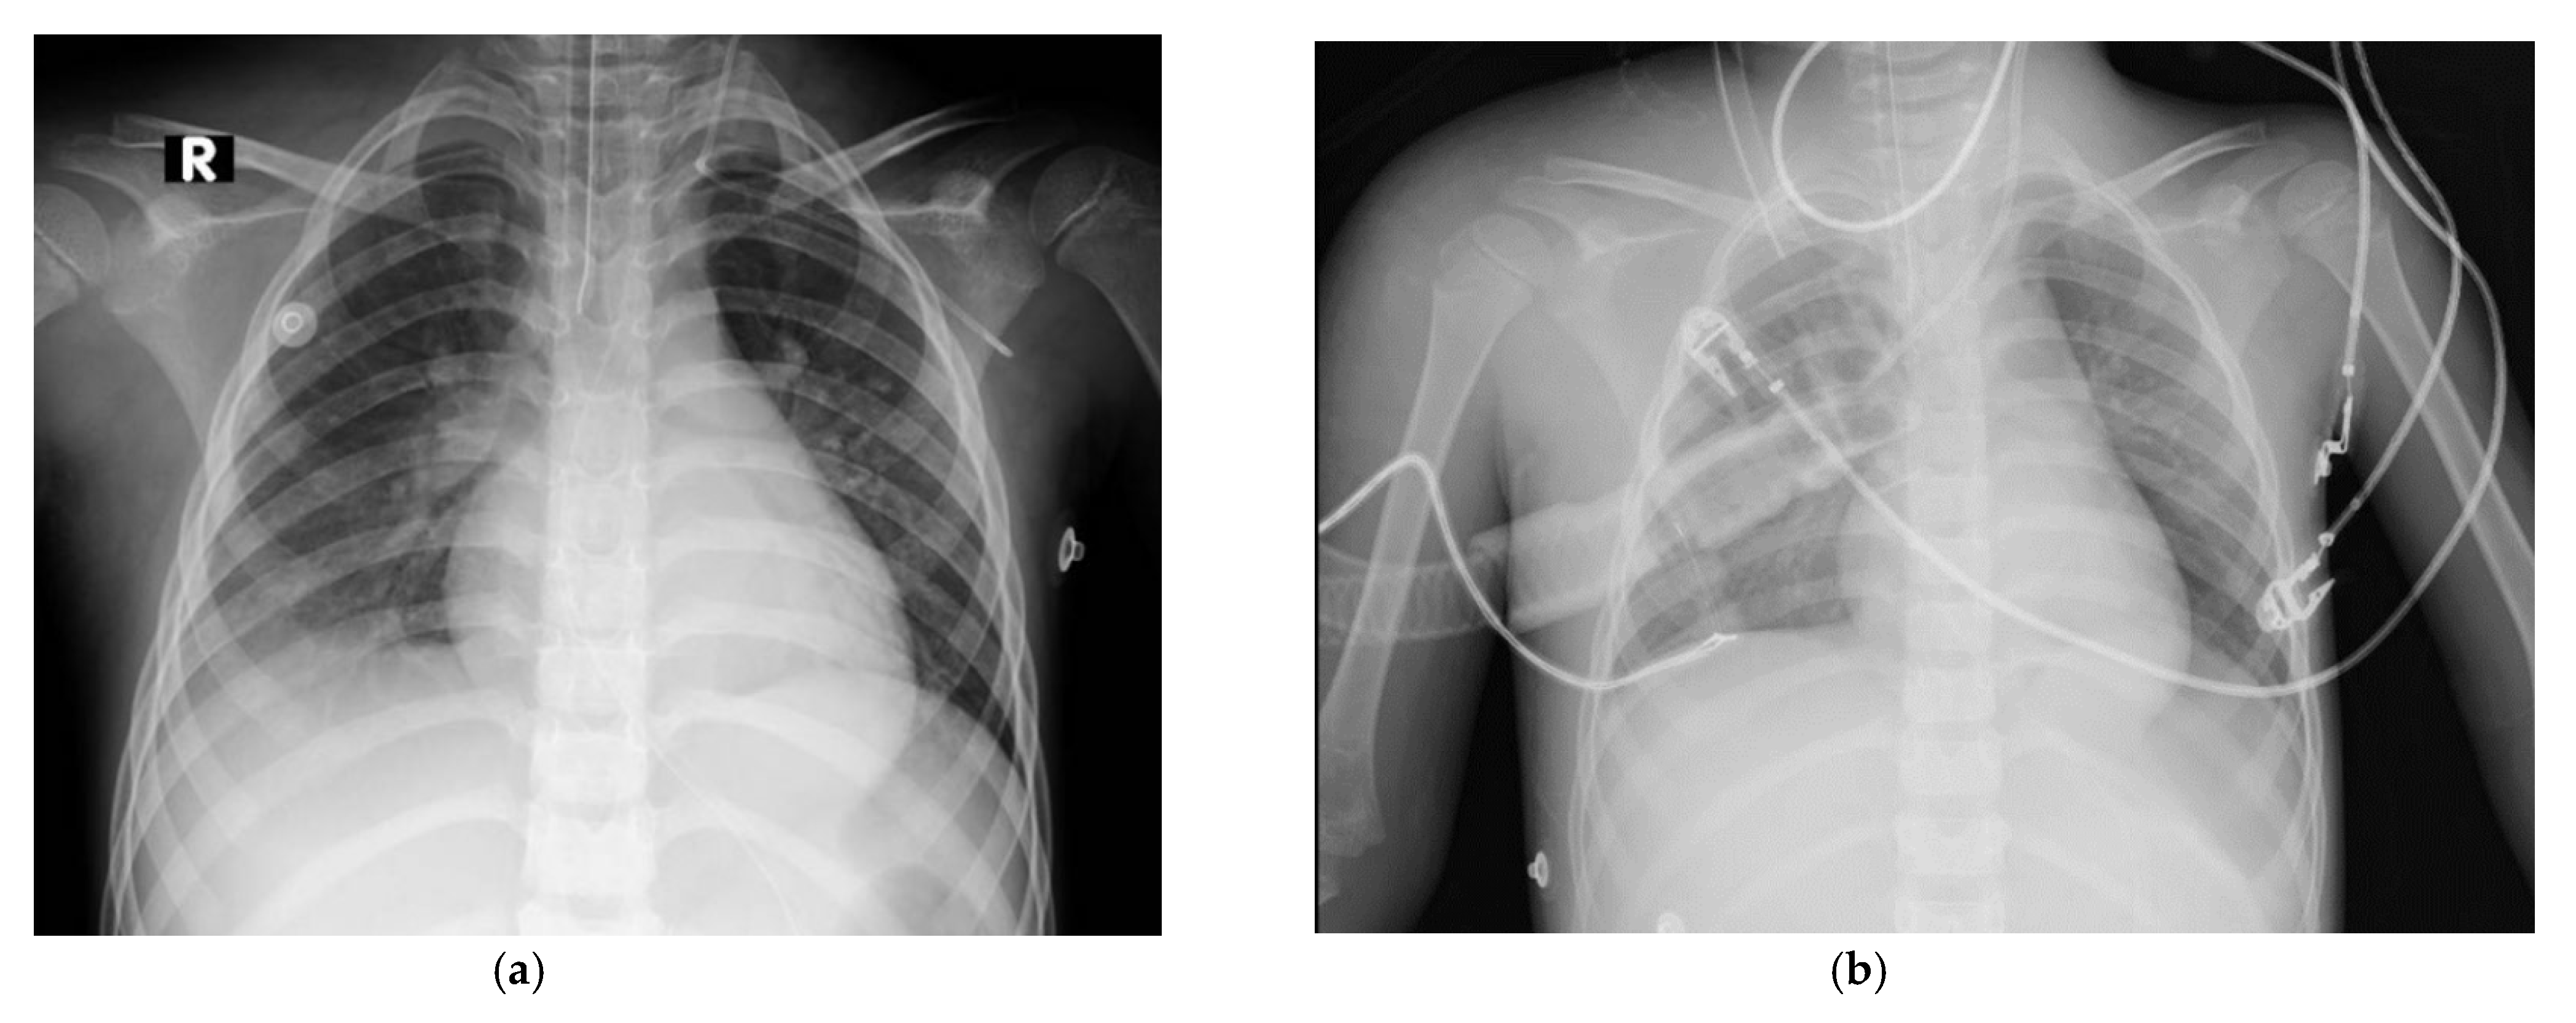

On the seventh day of hospitalization, the patient developed nosocomial pneumonia; antibiotic therapy was changed to piperacillin/tazobactam 80 mg/kg every 12 hours for 14 days. During a hemodialysis session, she experienced hemoptysis with a drop in hemoglobin to 6.5 g/dL and new bilateral alveolar infiltrates on chest radiography, consistent with diffuse alveolar hemorrhage (DAH) (Figure 3).

Figure 3. (a) Chest X-ray obtained at the time of admission; (b) Chest X-ray showing diffuse bilateral alveolar infiltrates.